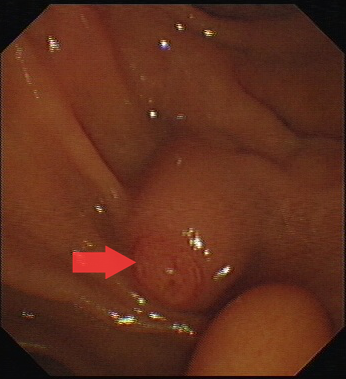

圖一:十二指腸乳頭。

第一步,先將十二指腸鏡到達(dá)十二指腸乳頭處,將通過(guò)十二指腸乳頭進(jìn)入膽總管取石